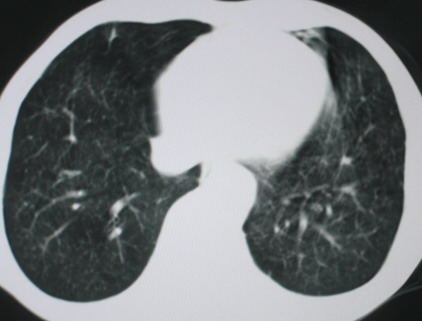

以下是引用医影拾贝在2008-6-3 18:48:00的发言:[br]双上肺弥漫性小结节影,纵隔窗内钙化淋巴结影,考虑血播性tb可能性较大,不除外肺ca可能

以下是引用卜一在2008-6-3 19:33:00的发言:[br]双肺结节,以双上肺分布为多,期间搀杂片状致密影及索条致密影。考虑:继发性肺结核伴血型播散可能性大。不除外肺泡ca的可能!另:椎体退变!

以下是引用panyishengct在2008-6-3 21:09:00的发言:[br]双上肺弥漫性小结节影,纵隔窗内钙化淋巴结影,考虑矽肺或/和tb可能性较大,不除外肺ca可能。腰椎考虑退变。 [br][br]